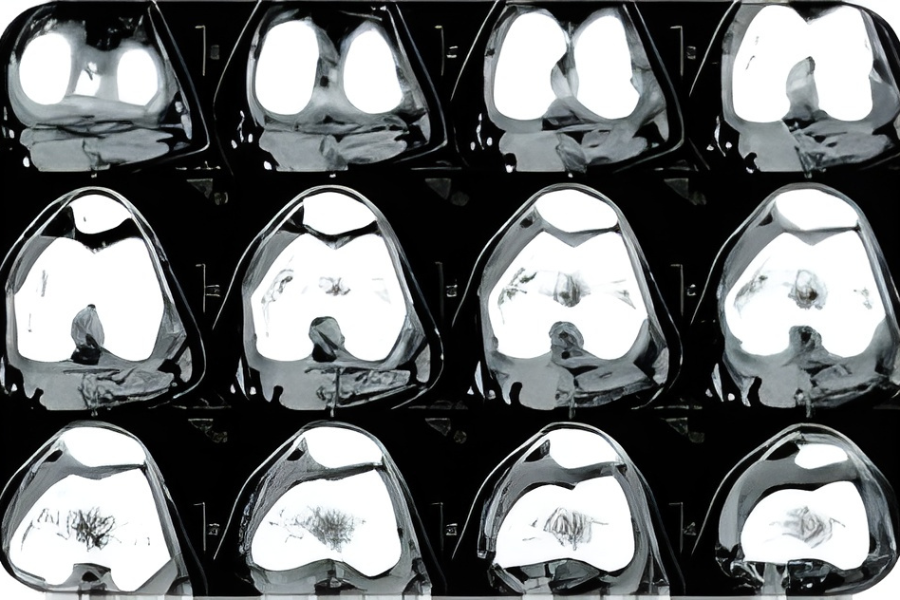

3D电脑断层扫描(CT)影像

| 术前影像检查 | 2D X光造影 | 2D X光造影 | 3D电脑断层扫描(CT) |